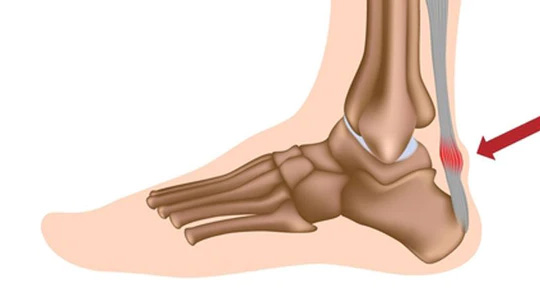

Achilles Tendonitis

When the Achilles tendon, the tendon that connects your calf muscle to your heel bone, becomes swollen, inflamed, and painful at the heel.

Pain and stiffness in the heel and along the tendon when walking, running, during the first steps in the morning, or after a night of sleep are the most common symptoms of Achilles tendonitis.

- Red, swollen skin over the tendon that is warm to the touch.